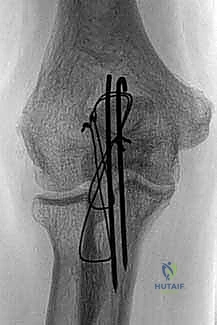

"Once we're happy with the reduction, we'll provisionally fix it with K-wires. I'm picking up two 1.0-mm smooth Kirschner wires. The trajectory is crucial here. We'll drill them obliquely from dorsal proximal to volar distal, aiming to exit the anterior ulnar cortex distal to the coronoid process. This provides a strong anchoring point in cortical bone and significantly limits the potential for pin migration."

• Drilling Technique: "Start drilling them parallel to each other, about 1-1.5 cm apart, crossing the fracture site. I'm using a low-speed drill to prevent thermal necrosis.

• Fluoroscopic Guidance: "Let's get a lateral fluoroscopy shot to confirm our K-wire trajectory and ensure they are not entering the joint and are indeed exiting the anterior ulnar cortex distal to the coronoid. This is a critical step, fellows. Intra-articular K-wires are a major pitfall and will lead to pain and arthrosis."

Image

TECH FIG 1 • (continued) C. Two 1-mm Kirschner wires are drilled obliquely across the fracture site so that they exit the anterior ulnar cortex distal to the coronoid process. ( A,B: Copyright David Ring, MD.)

* Retraction: "Once both wires have breached the anterior ulnar cortex, we need to retract them slightly, about 5 to 10 mm. This is in anticipation of later impaction of their proximal ends, ensuring they don't protrude or irritate the soft tissues."